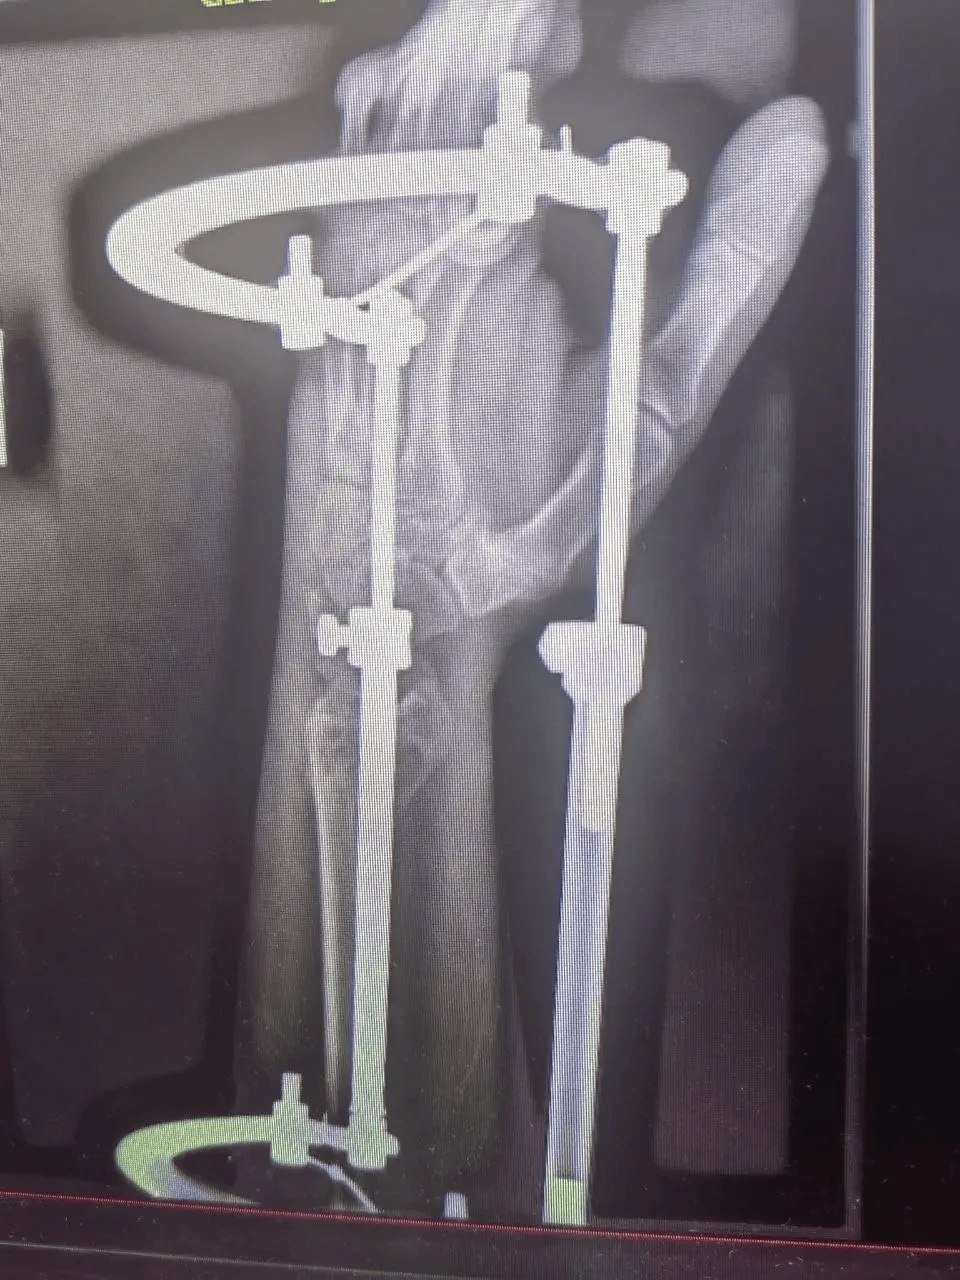

Мужчина 1972 года рождения получил множественные переломы и другие серьёзные травмы. Его лечением занималась команда специалистов разных профилей. Челюстно-лицевые хирурги провели шинирование, травматологи-ортопеды выполнили операцию на правой локтевой кости и восстановили левую лучевую. Также пациент проходил лечение у нейрохирургов и неврологов.